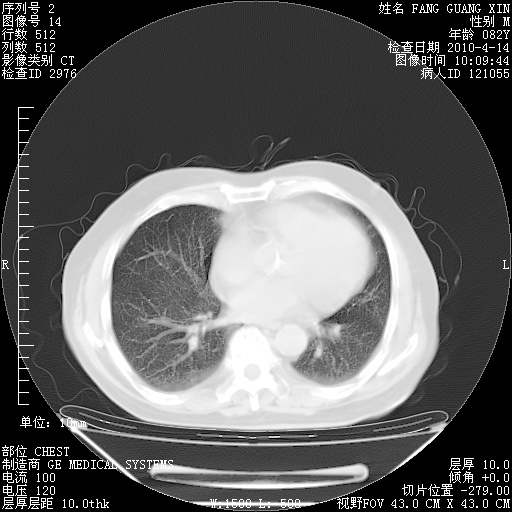

4月14日肺部CT

肺部CT平扫未见异常。